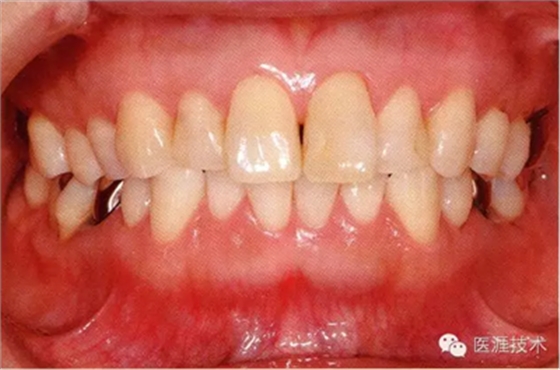

18歲男性的健康口腔內(nèi)部

圖為18歲男性,無特殊全身疾病,不抽煙。持續(xù)保養(yǎng)10年。牙菌斑控制比以前好,因刷牙稍稍過度臉頰側(cè)有牙齦萎縮傾向,但牙齒及牙周組織仍保健康。